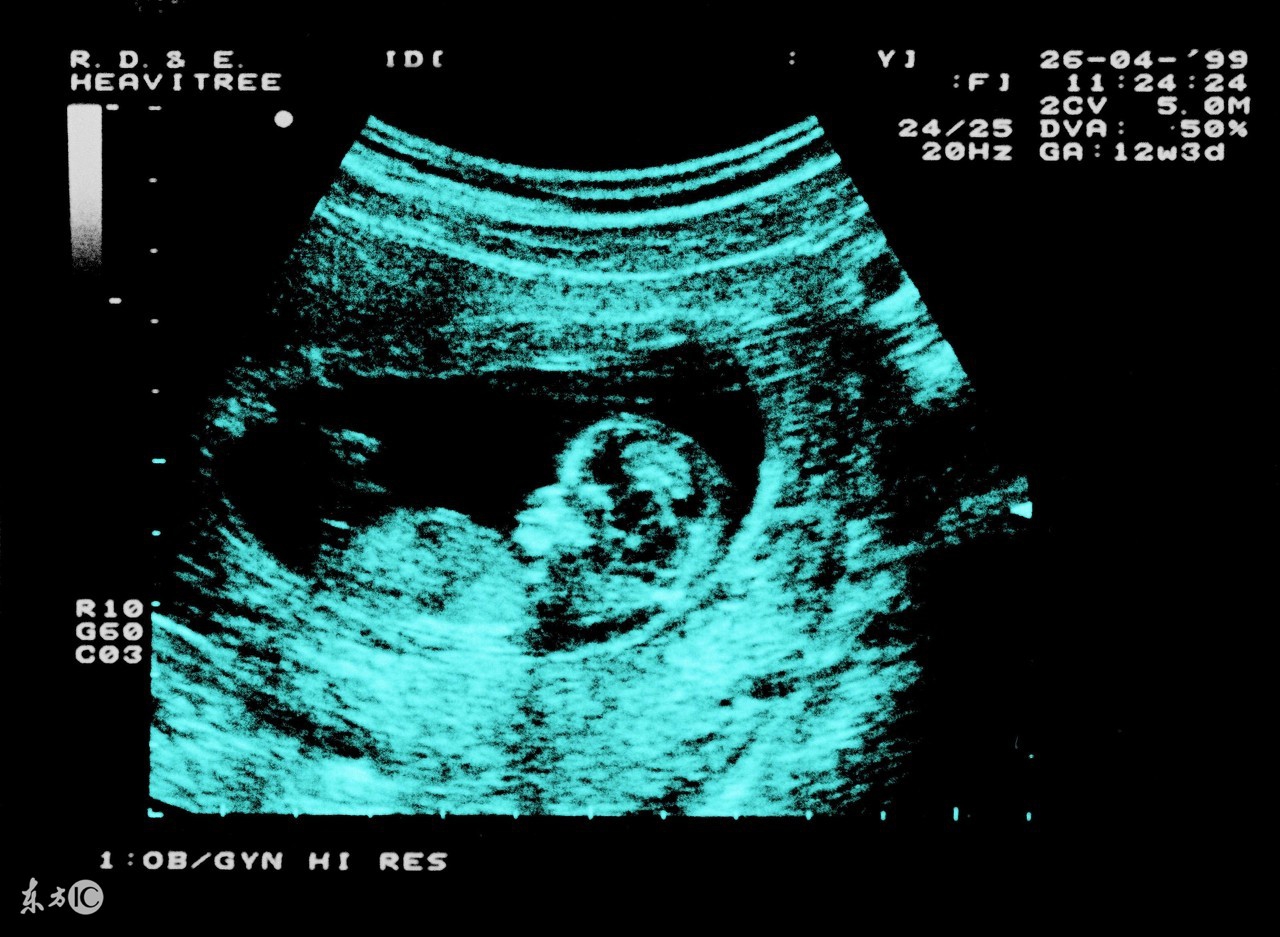

妊娠28周后经腹部、阴道、B超检查可检查是否为异常胎位。妊娠28周以前,由于羊水相对较多,胎宝宝又比较小,在子宫内活动范围较大,所以位置不容易固定。妊娠32周以后,宝宝生长迅速,羊水相对减少,此时胎宝宝的姿势和位置相对固定。所以在孕32周以后,如果宝宝还是“胎位不正”就基本上等于确定了,当然也不排除极少数胎宝宝来个“意外之举”。所以胎位不正最合适的纠正时间为孕30-32周之间。